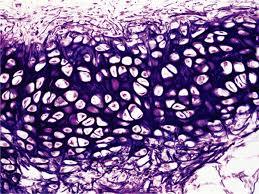

1. Tejido: Un tejido es un conjunto de células similares que suelen tener un origen embrionario común y que funcionan en asociación para desarrollar actividades especializadas.